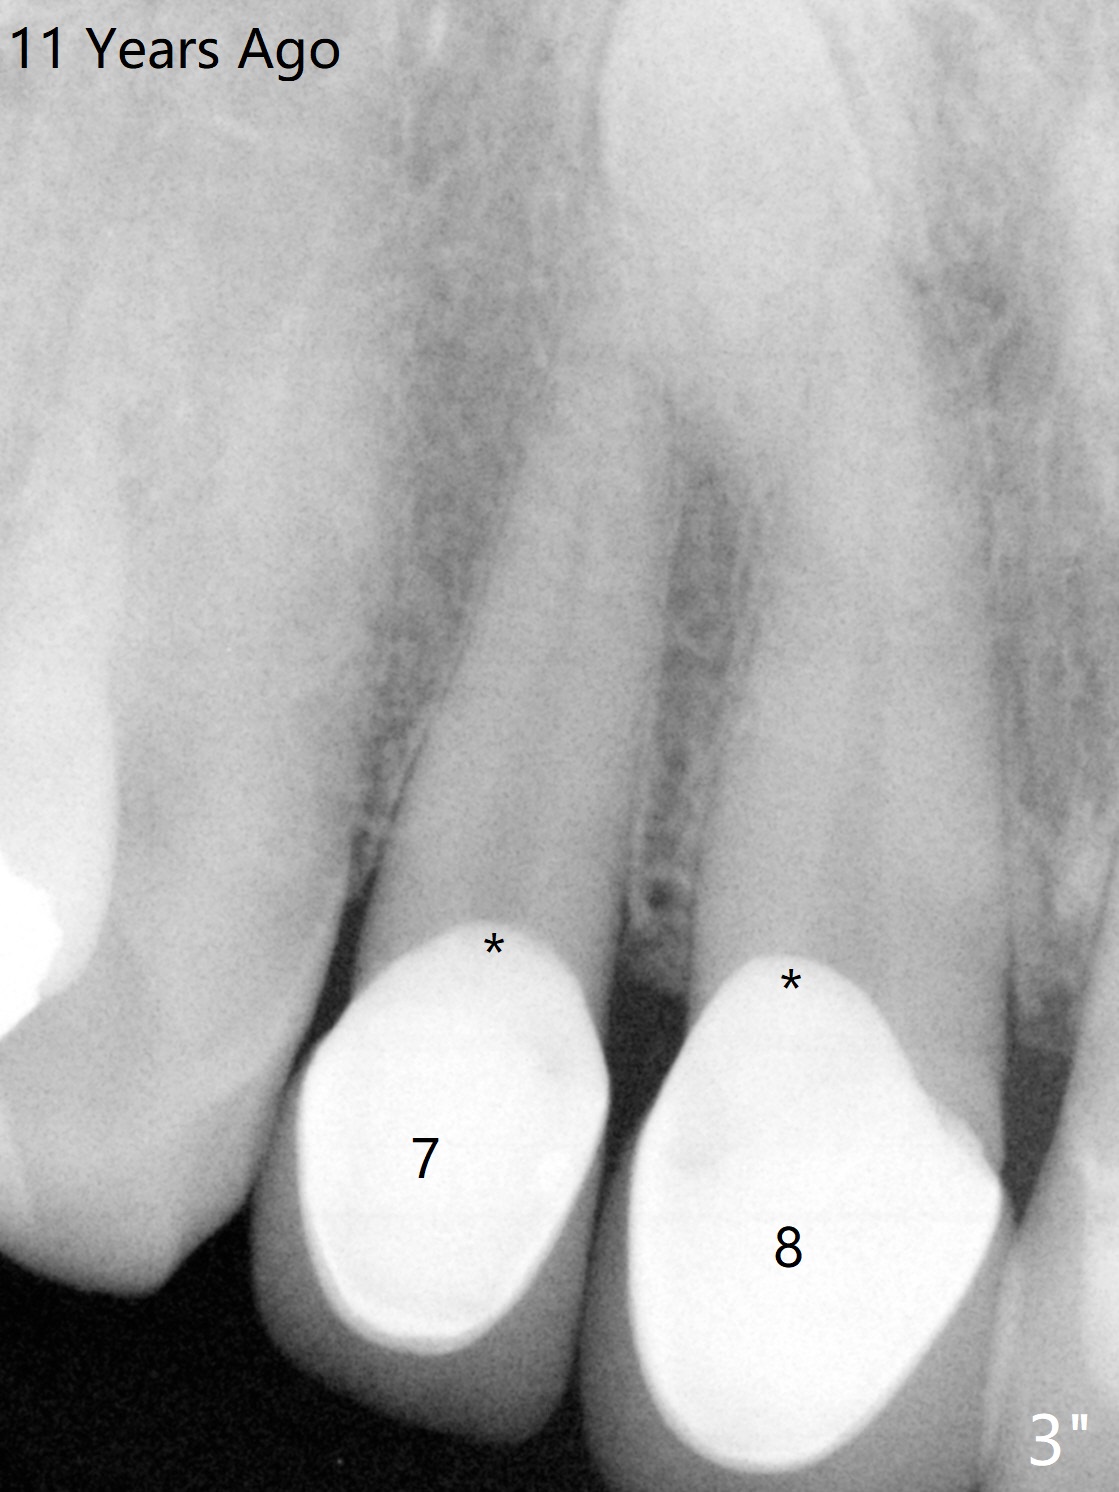

A 58-year-old man fractures the tooth #9 equigingival and fiber post (Fig.3 *, as compared to Fig.3" and 3'). * in Fig.3" overextended buccal margin of the crowns, as related to gingival inflammation. > in Fig.3': lack of ferrule effect.